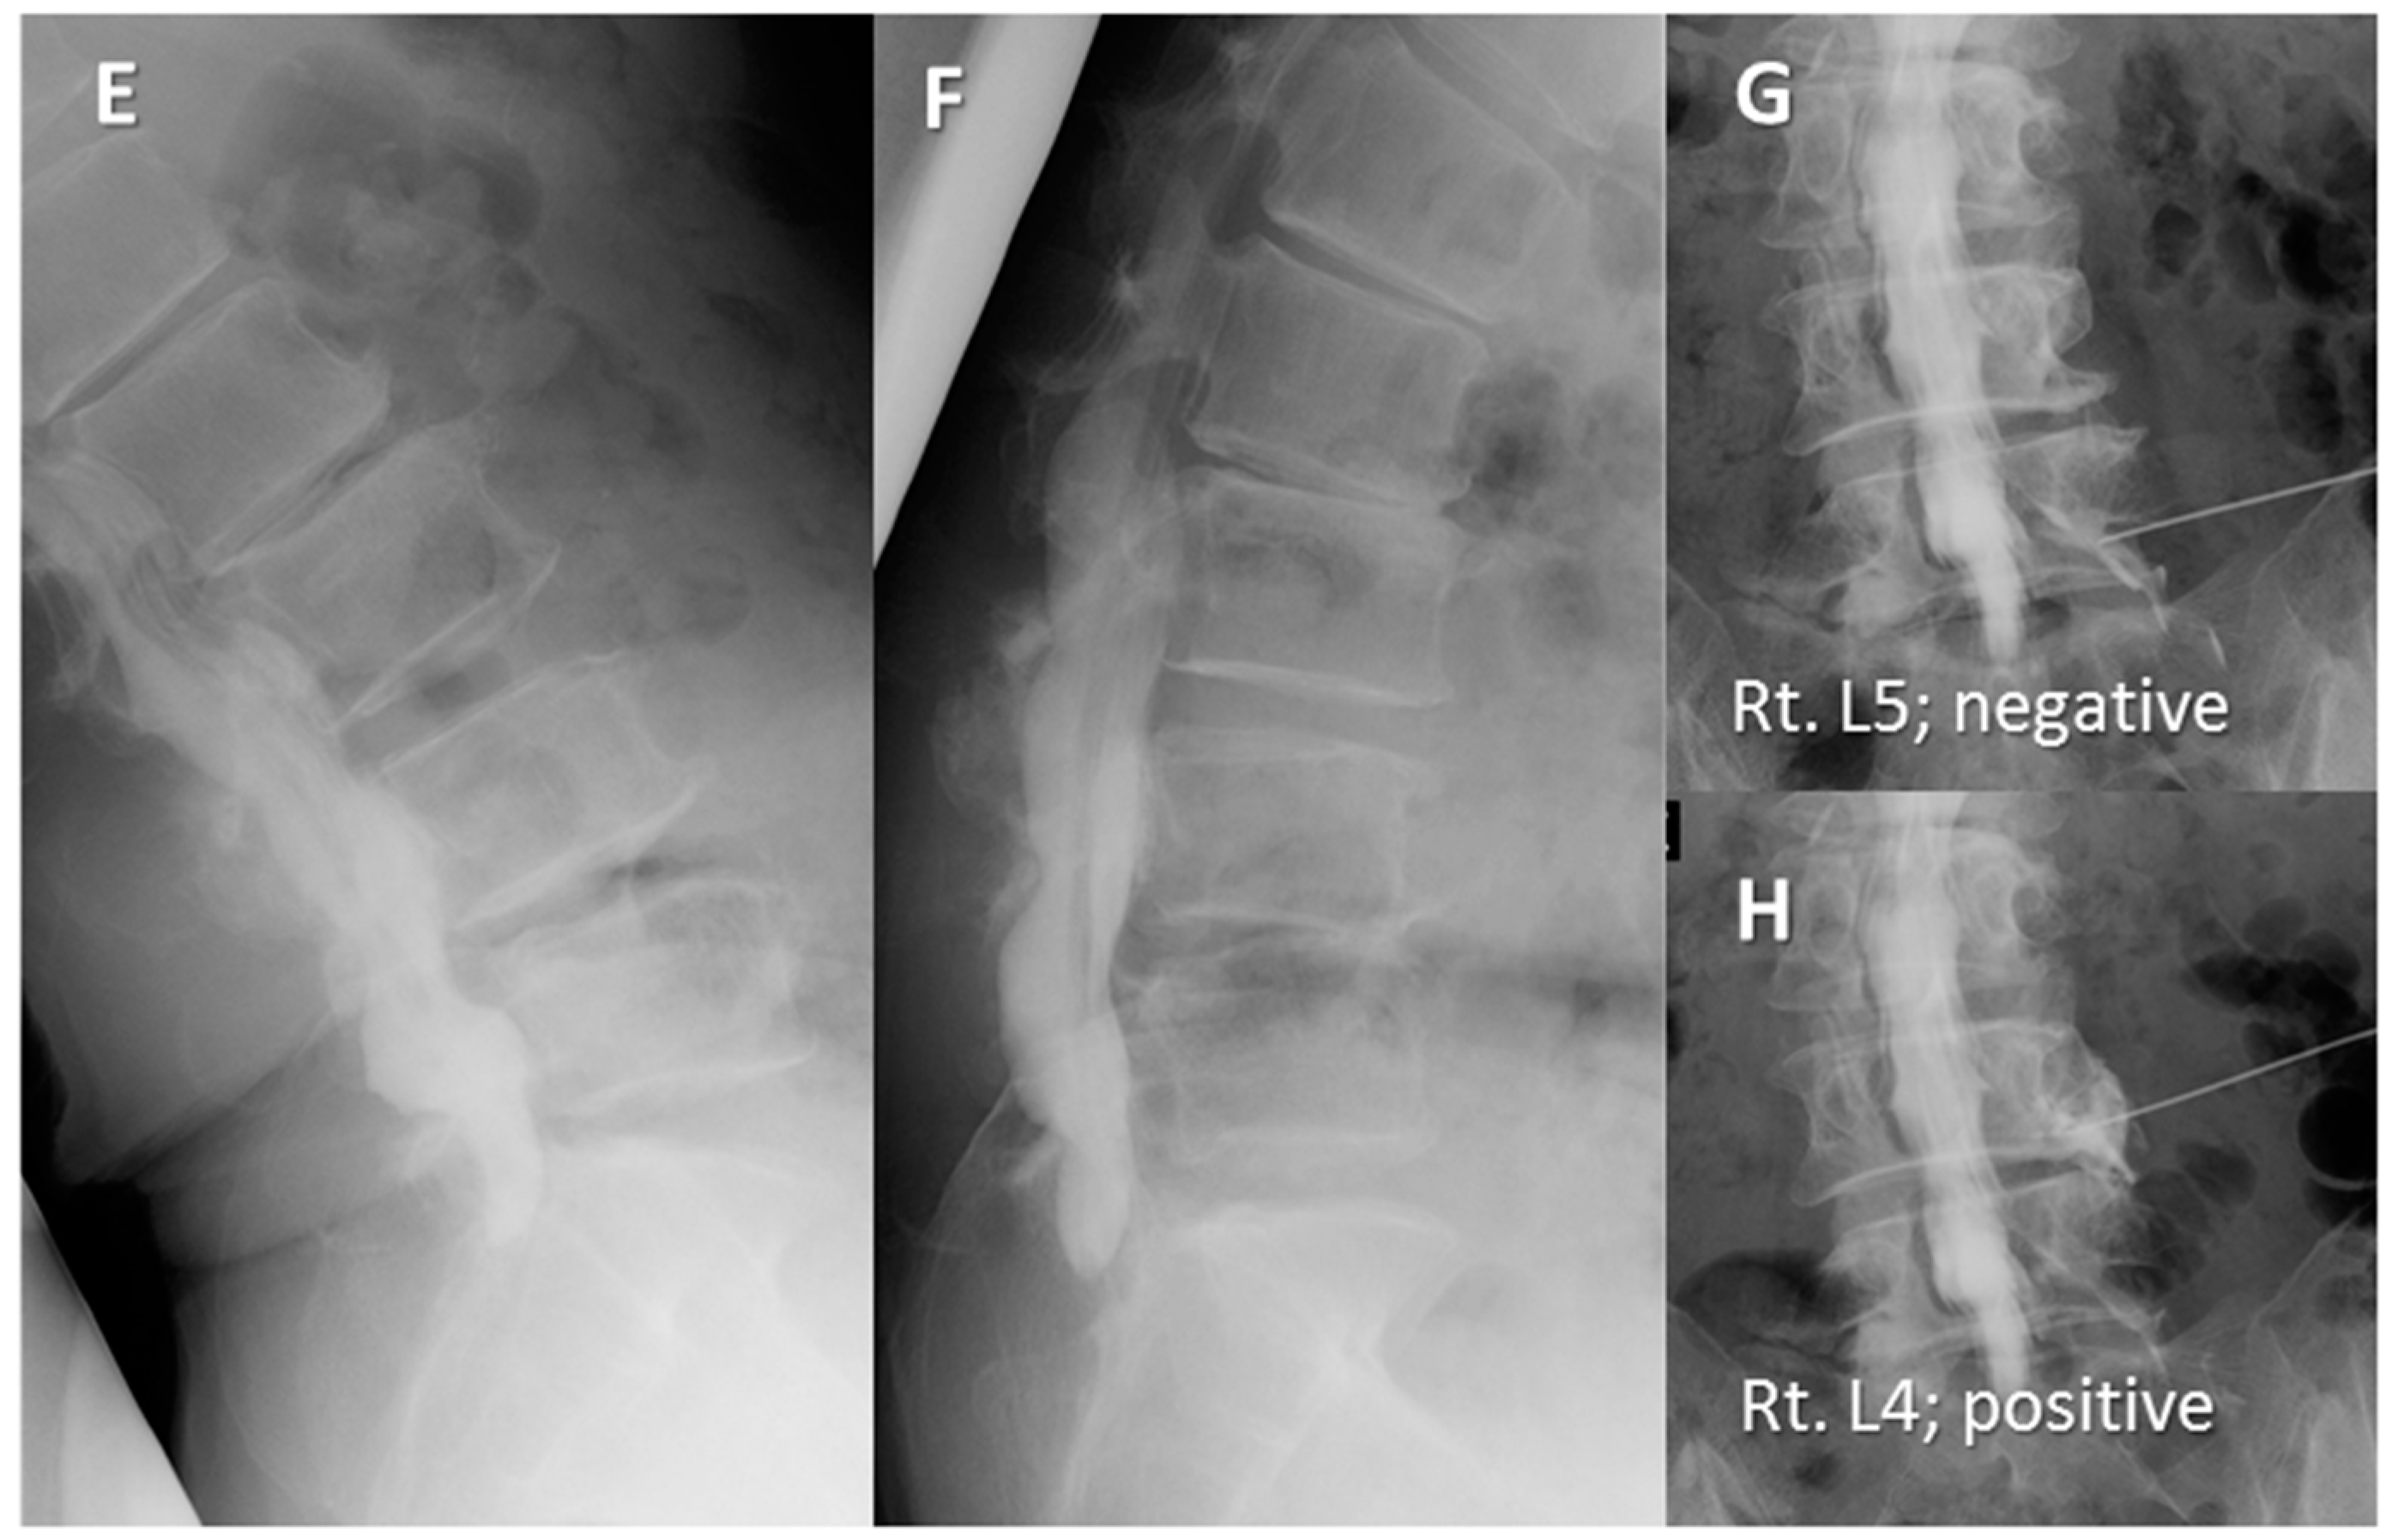

Case Presentations